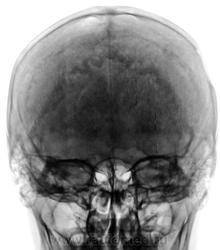

- https://radiomed.ru/sites/default/files/styles/case_slider_image/public/user/12/3.201201010032_0.jpg?itok=rR-O_KyX